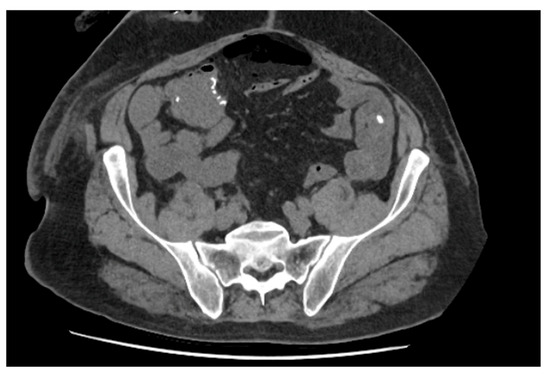

2.1.2. Case 2